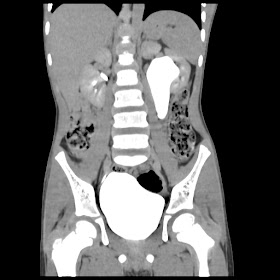

A 07 years old child with left side of abdomen pain

current CT images: